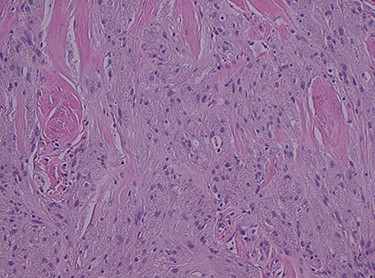

Histopathology of the right hemicolon found five firm nodules in the caecum and an additional seven polyps in the ascending colon macroscopically. Microscopically, a total of eight lesions in the caecum and ascending colon were found to be GCTs, varying in size from 1 to 7 mm. They were submucosal with intact covering mucosa (Figs 1 and 2). Tumour cells had periodic acid-Schiff (PAS)-positive granular cytoplasm and small nucleoli (Fig. 3). Immunohistochemical staining was positive for S-100 (Fig. 4) and inhibin. Twenty-four lymph nodes identified showed no abnormality. Spindling was seen in some tumours in this case, but overall, there are less than three worrisome features, and as such, these GCTs were considered atypical. Other polypoid lesions identified included two hyperplastic polyps and a submucosal lipoma.

Histologically GCTs are characterized by plump neoplastic cells with abundant eosinophilic granular cytoplasm. Immunohistochemistry for neural markers, S-100 protein and NSE are diffusely positive, while other markers include inhibin, calretinin and nestin [2, 4]. Fanburg-Smith et al. [3] described microscopic criteria to predict malignant potential, where GCTs meeting three or more criteria were classified as histologically malignant.